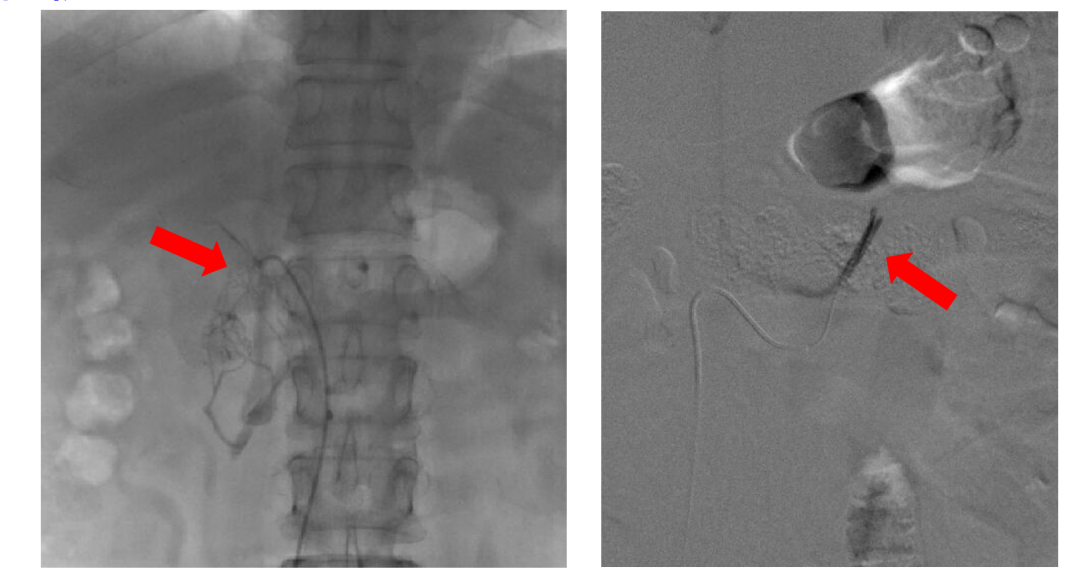

如果筛查结果阳性,医生会酌情安排进一步的确证试验(如卡托普利试验、盐水负荷试验等)和分型定位检查(如肾上腺CT、肾上腺静脉采血),以确定是单侧还是双侧病变,从而指导治疗选择。分侧肾上腺静脉取血(AVS)是原醛分型定位诊断的“金标准”,对于患者治疗策略选择非常重要。

(分侧肾上腺静脉取血,图片来自杨宁医生)